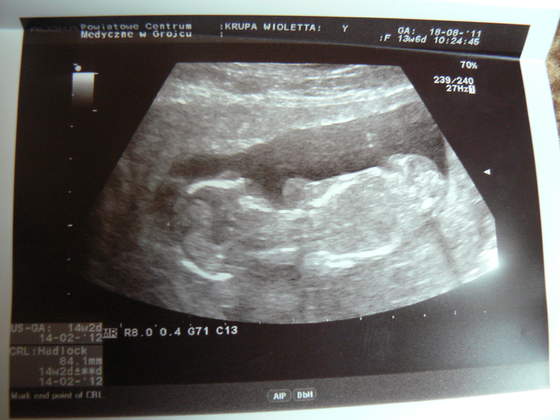

Moje maleństwo ma już 8,5 cm długości, więc jest już kawałem dzidziola

Maleństwo machało dzisiaj do mnie łapkami i nie za bardzo chciało współpracować z panem doktorem, który robił USG!!!

A oto moje maleństwo:

Zobacz załącznik 382631Zobacz załącznik 382632Zobacz załącznik 382633